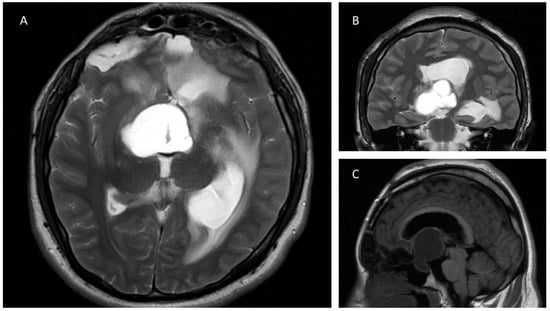

3.2.2. Case 2